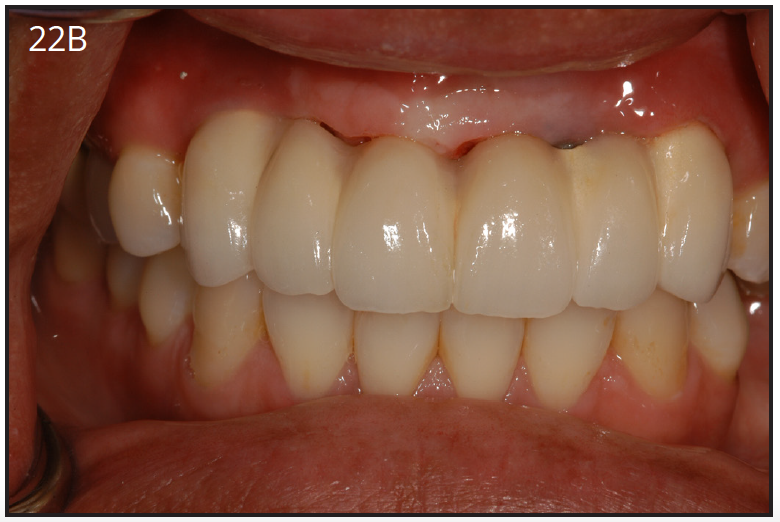

The implant prosthesis delivery appointment is similar to that of a crown and bridge. (Figure 22B) If the prosthesis is screw retained, then no cement is necessary and an occlusal filling material, such as composite, is necessary. After bite check, the patient is taught how to maintain the restoration. (Figure 22C)

Figure 22B – Metal-free fixed partial denture cemented on abutments

Figure 22B